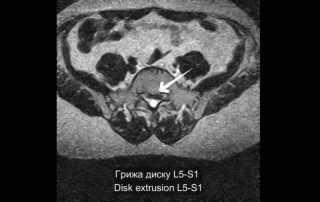

Леонтьєв Олексій2026-01-05T18:54:24+02:00У цьому відео ми демонструємо сучасний малоінвазивний підхід до лікування стенозу поперекового відділу хребтового каналу на рівні L2–L3 у пацієнтки 75 років. Операція виконана методом унілатеральної біпортальної ендоскопії [...]